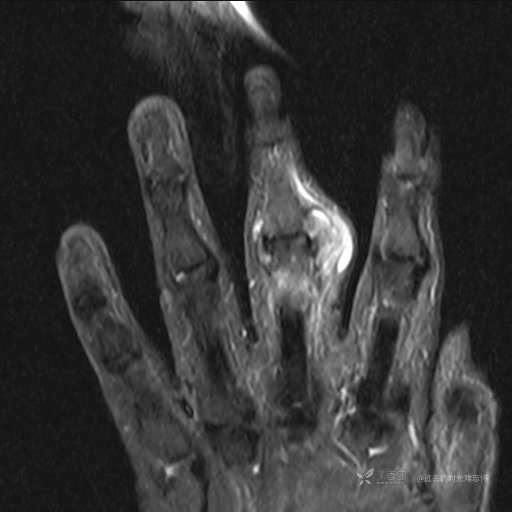

患者性别:女

患者年龄:59岁

主诉: 手指肿胀2年,其间明显肿胀,抗炎后肿胀减轻,近几日肿胀疼痛加重。

T1

提示:小指是伪影。